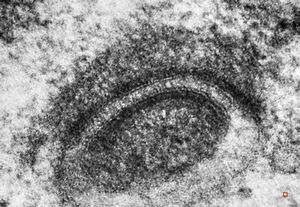

F,50y. | progressive multifocal leukoencephalopathy- viral particles in a glial cell

F,50y. | progressive multifocal leukoencephalopathy- viral particles in a glial cell

F,50y. | progressive multifocal leukoencephalopathy- viral particles in a glial cell